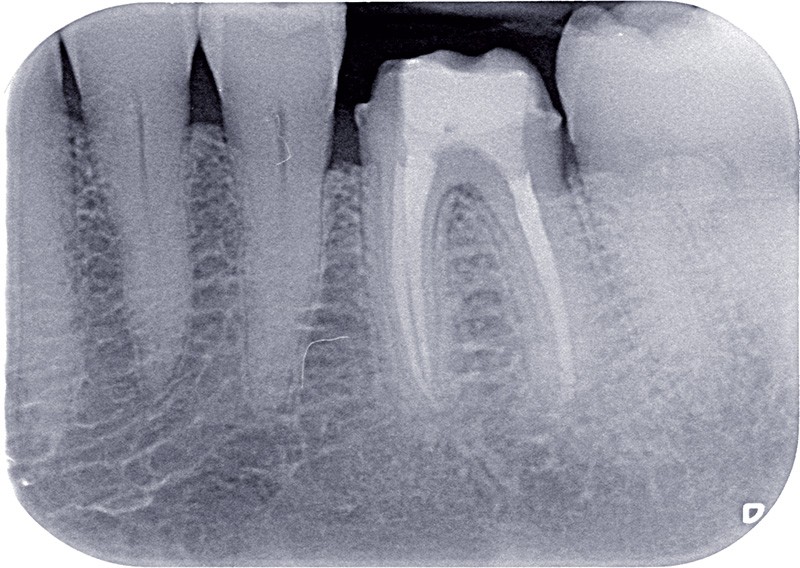

Dans ces situations, le praticien est conduit à dépulper et à restaurer les dents traitées endodontiquement. Les traitements doivent alors s’inscrire dans le concept du continuum endo-restaurateur qui a été défini comme étant « le processus spatio-temporel sans interruption ni rupture qui débute par l’accès à l’endodonte et s’achève avec la mise en place de la restauration prothétique d’usage » (1). Il existe bien une continuité, du traitement endodontique à la restauration fonctionnelle d’usage qui conditionne le pronostic et les résultats du traitement à long terme (fig. 2).